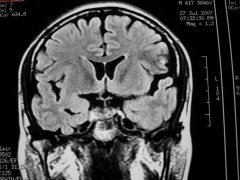

脑囊肿的概述

脑囊肿是指脑组织与其附属物形成水囊性肿物,并产生不同程度的脑......[阅读全文]